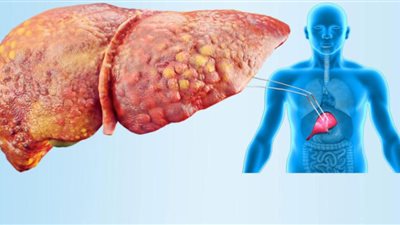

ما هو مرض الكبد الدهني؟

الكبد هو أكبر عضو داخلي في الجسم، ويحدث مرض الكبد الدهني عندما يكون هناك الكثير من الدهون المتراكمة في الكبد لأسباب مختلفة.